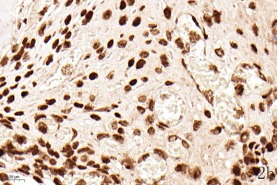

NDN(Necdin)属于黑色素瘤抗原(MAGE)家族,由60多个基因构成共享高度保守的MAGE同源结构域(MHD)[6,7]。最近几年的研究提出NDN是一种新的抑癌基因,其在卵巢癌[8]、乳腺癌[9]和黑色素瘤[10]等的组织和细胞系中低表达,过表达NDN可以抑制其生长,但NDN在骨肉瘤中的作用及机制尚不清楚。为探讨NDN在骨肉瘤中的作用及途径,我们收集了骨肉瘤患者的石蜡标本以及临床信息,对其进行了免疫组化检测及生存分析。通过对骨组织和骨肉瘤HE染色发现,骨组织组,骨密质呈板层状,陷窝中可见骨细胞呈梭形排列( 图1 a 1b) ;骨肉瘤组,瘤细胞呈多角形,核大深染,核分裂多见,瘤细胞呈车辐状排列,瘤细胞间可见少量肿瘤性骨质形成(图1c1d)。同时通过免疫组化发现,NDN表达主要位于细胞的胞核中。NDN在骨肉瘤组织中的表达率为29.4%(15/51)(图1c1d),明显低于瘤旁骨组织阳性表达率80%(8/10)(图1a1b)。